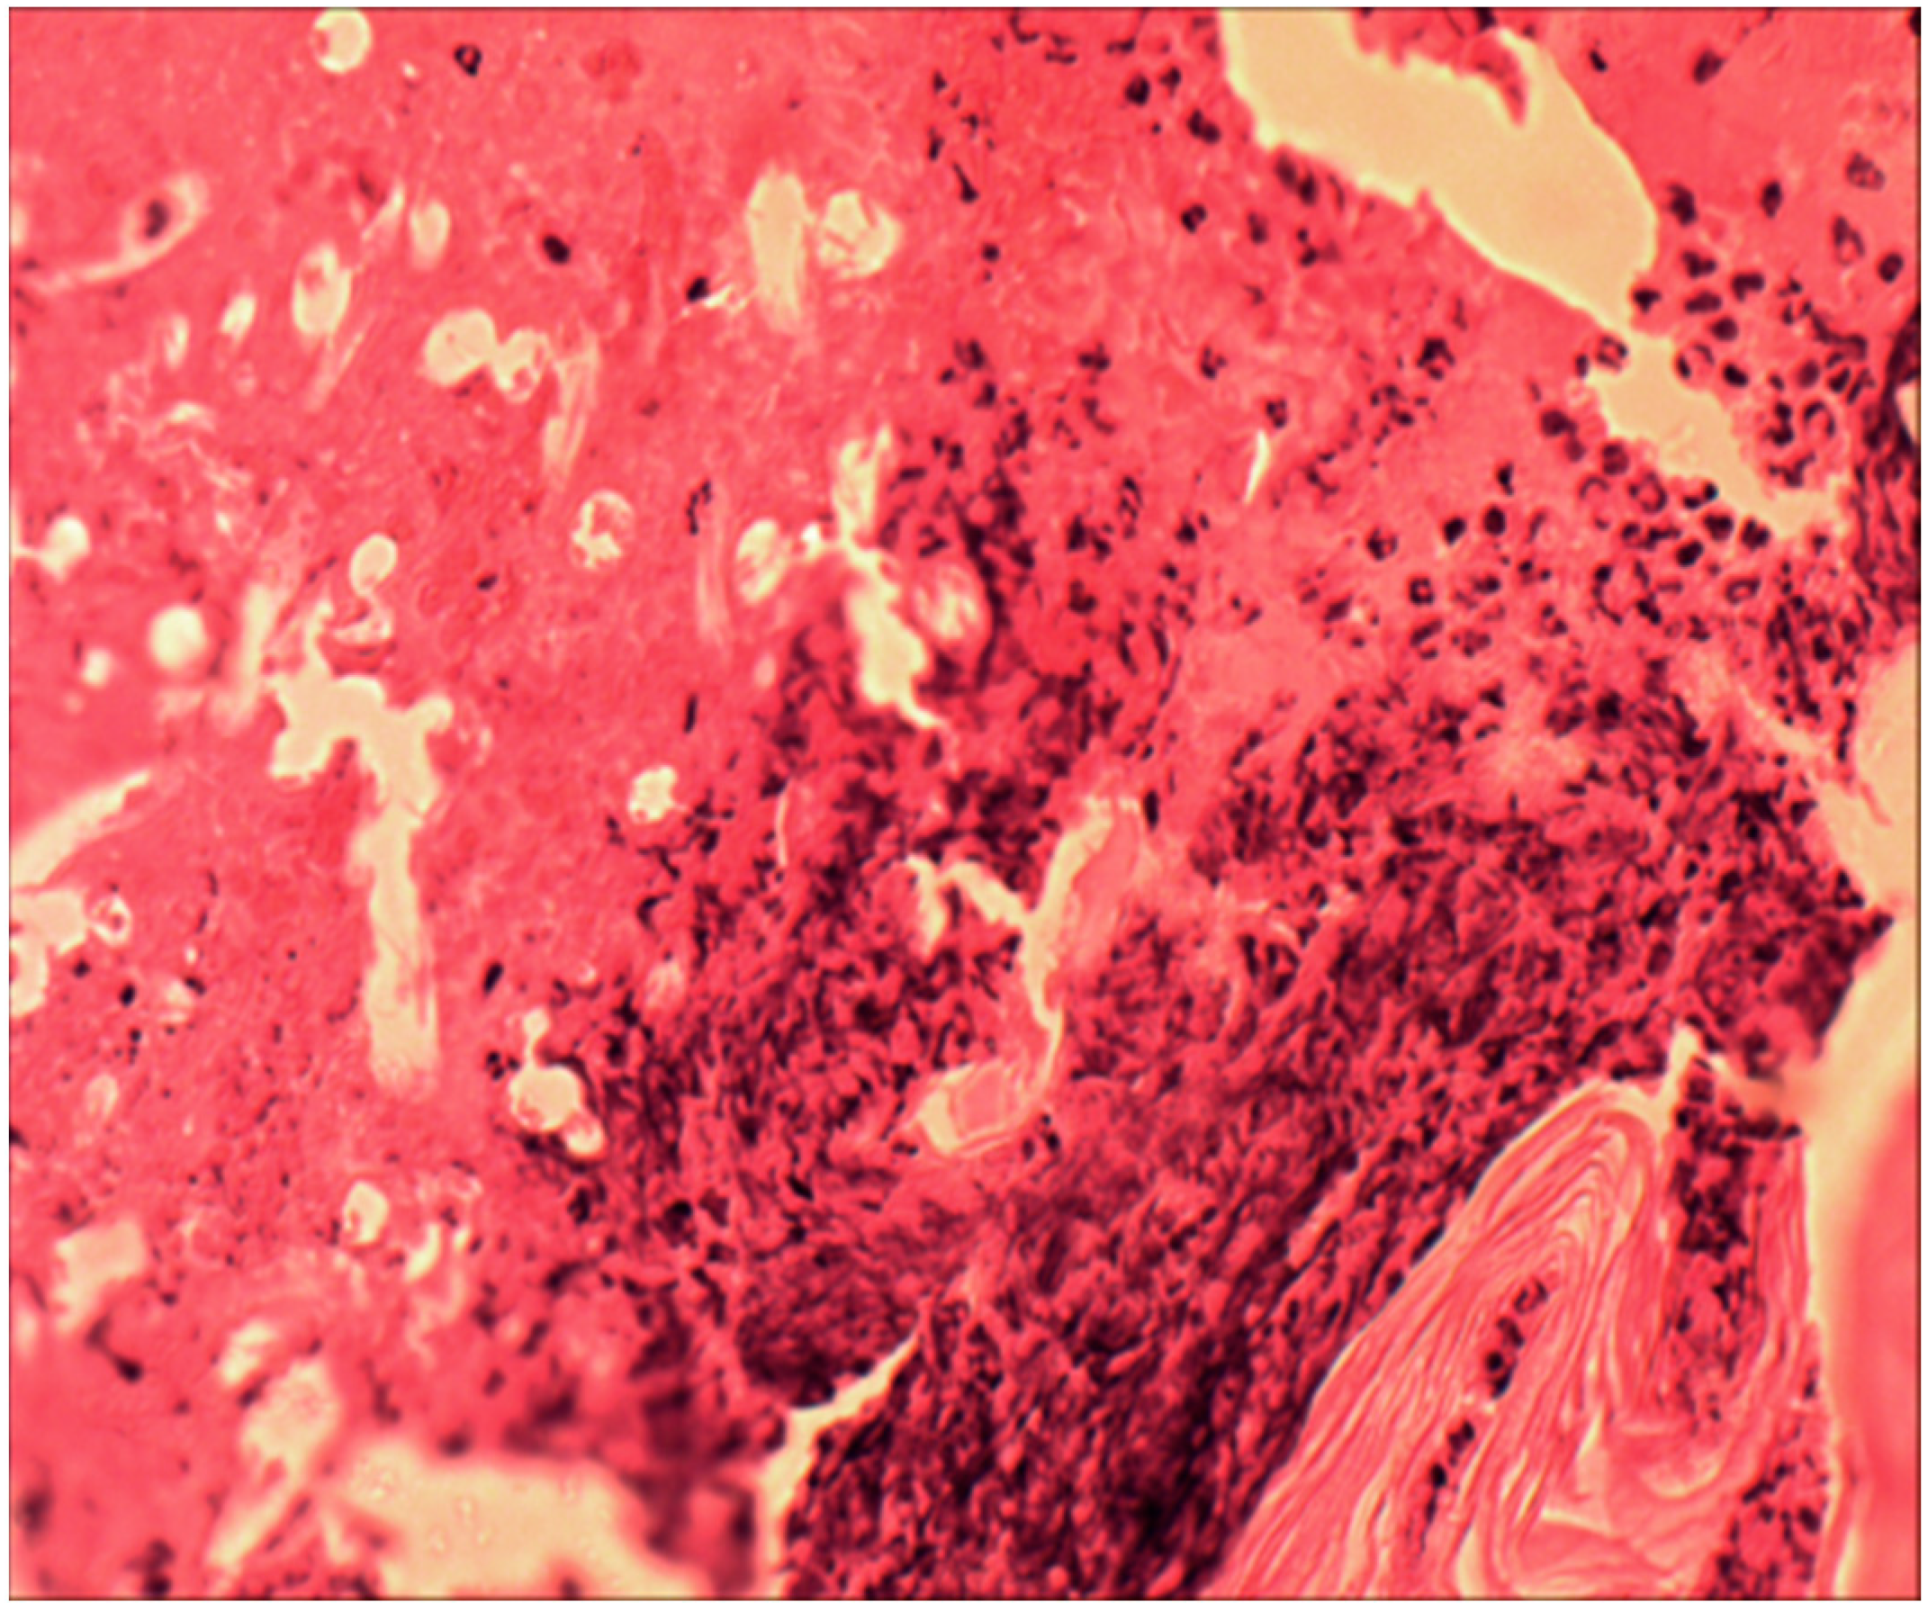

- Using morphometry, it was established that this polymer begins to biotransform one month after implantation, when the transformation of the synthetic matrix begins under the influence of physicochemical degradation processes and biological transformation processes, accompanied by the absorption of released biopolymer chains by macrophages. Before this period, an inflammatory infiltrate was formed along the border with the material, which after one month, due to biotransformation processes, moved into the depth of the polymer matrix, increasing the area of inflammation. In terms of qualitative composition, in the first two weeks, the inflammatory infiltrate was mainly represented by macrophages, leukocytes, and lymphocytes. After one month, the number of inflammatory cells decreased, especially macrophages—they were partially replaced by fibrocytes and fibroblasts. Subsequently, the composition of the infiltrate changed little.